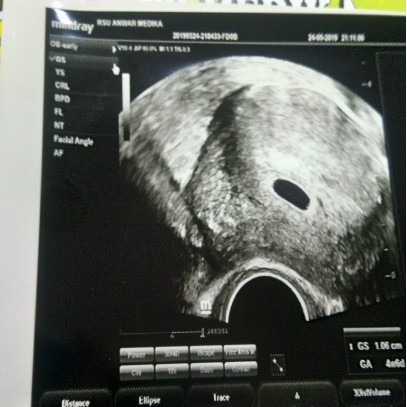

asskum..pagi bunda" sya bru hamil 5w kmren di USG msih terliht kantonya sja semoga kontrol lusa sudah terliht perkmbngan nya dan sehat amiin

asskum selamat pgi bunda" sya bru hamil 5w kren pas konttol pertma sya di USG tpi msih terlihat kantung nya sja..semoga di kontrol yang ke 2 udh terlihat dan semoga sehat amiin...